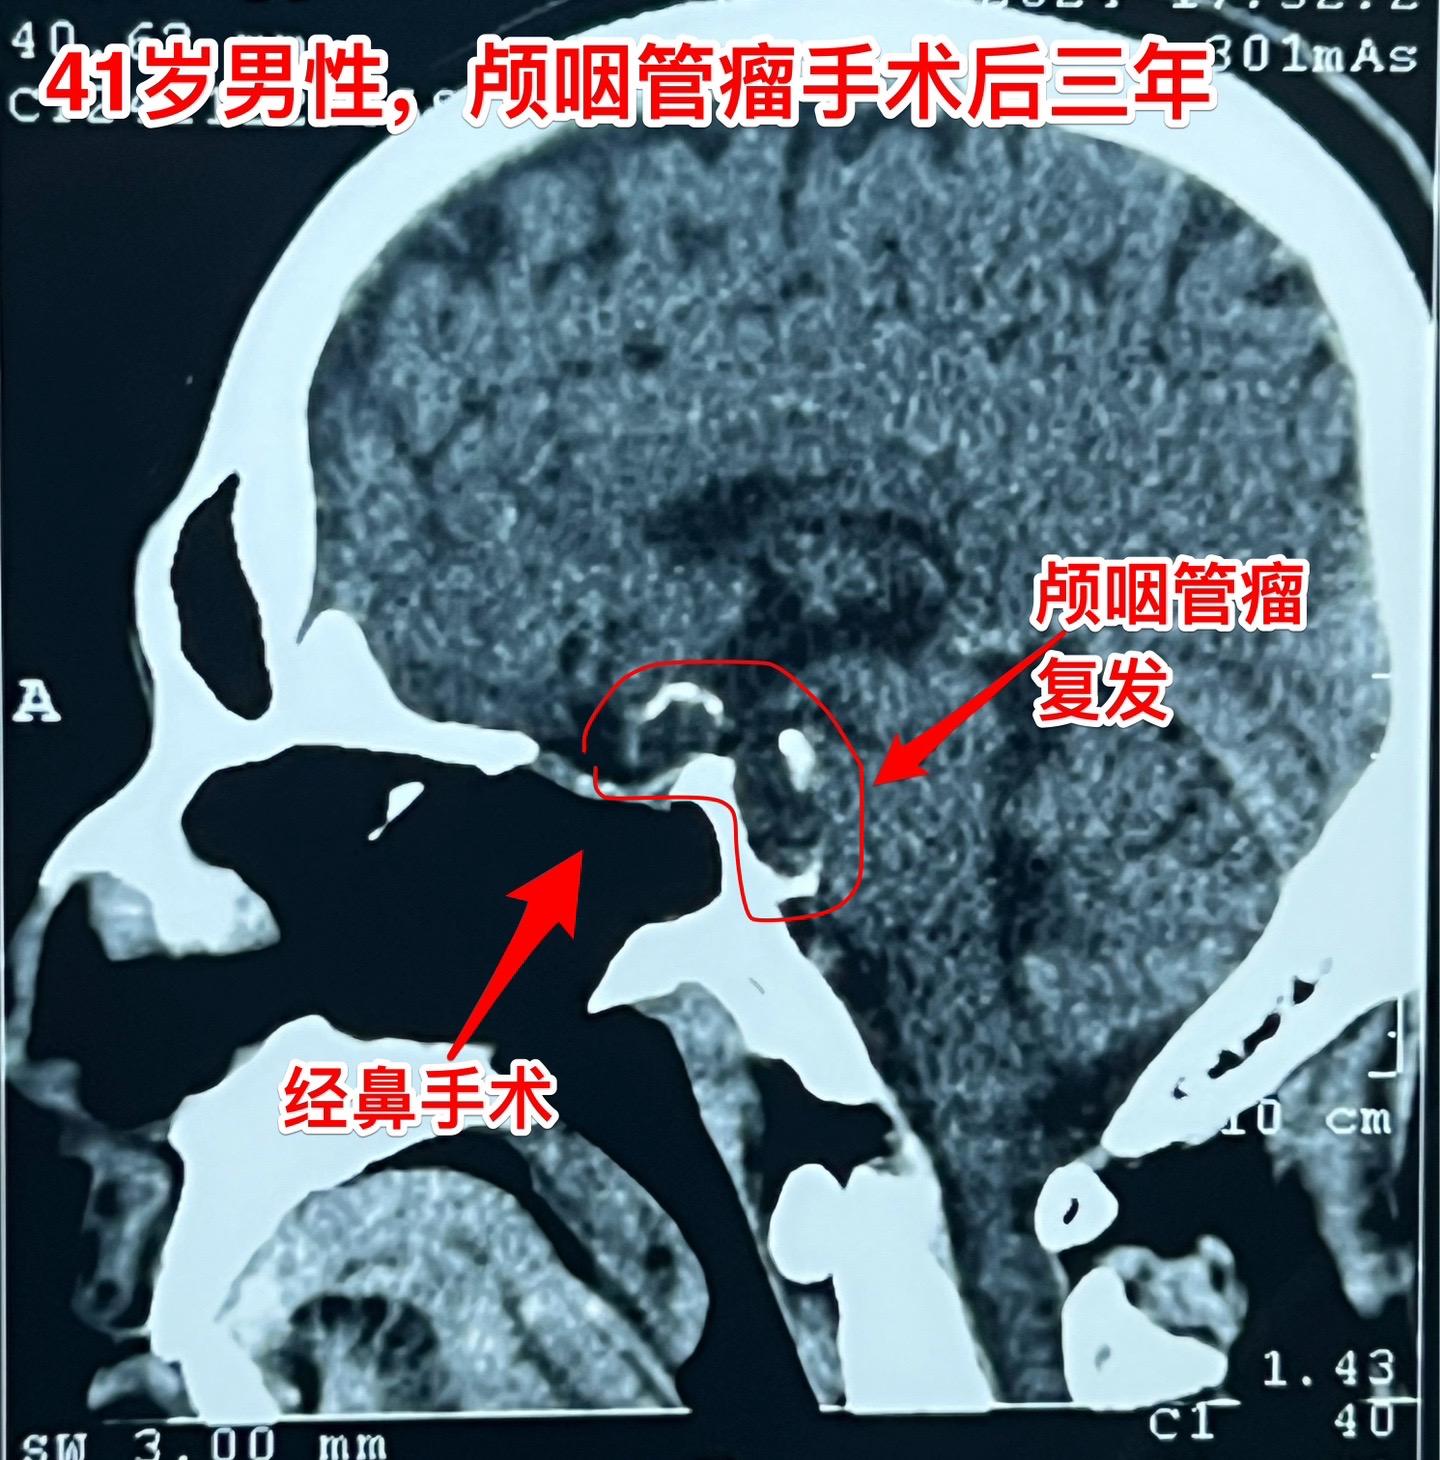

又一个经鼻手术后复发的颅咽管瘤。41岁的大连市男性,三年前因视力下降在...